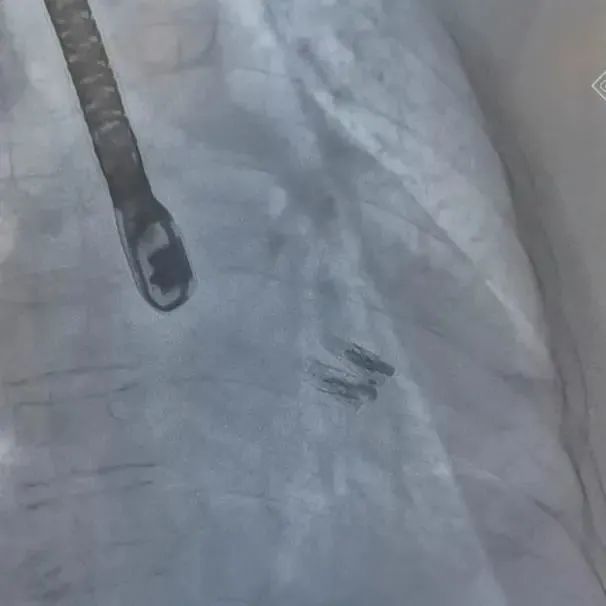

术中,郭延松教授团队经股静脉穿刺房间隔,将器械通过输送系统送入左心房,到达二尖瓣膜反流处。在经食道超声心动图及DSA引导下,手术团队反复评估二尖瓣膜脱垂范围、抓捕位置、反流程度,精准夹合,成功植入DragonFly瓣膜夹。患者术后第1天便可下床活动,气促等心衰症状也得到了明显改善。

▲二尖瓣瓣膜夹释放